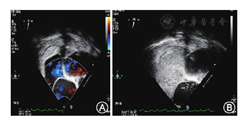

46例中患者中,A组17例,13例(13/17)右心声学造影无右向左分流(图1),4例(4/17)1级分流。B组20例,100%发生右向左分流,其中5例(5/20)1级分流,15例(15/20)2~3级分流(图2)。C组9例,100%发生右向左分流,其中2例(2/9)1级分流,7例(7/9)2~3级分流(图3)。

随着年龄的增长,由于心脏退行性变及高血压、冠心病、心律失常等因素造成左心室舒张功能受损,左心室充盈压升高,从而引起左房压增高,久之导致左心房增大[9],左、右心房压差增大,如果合并卵圆孔未闭,左向右分流增多,可表现为明亮的左向右分流。研究中彩色多普勒明显左向右分流的患者多合并左心系统异常,如冠心病、左心室肥厚等。在右心声学造影过程中,此类患者大部分(13/17)无右向左分流,仅4例有1级分流。同时,右心声学造影无右向左分流患者左心房前后径比有右向左分流患者左心房明显增大,说明此类患者左心房压力增高,通过valsalva动作也不能使右心房压力超过左心房,即使超过也很微弱。产生反常栓塞的必备条件[10,11]是:(1)体内存在异常通道;(2)右心房压力增高,超过左心房;(3)静脉系统栓子的存在。